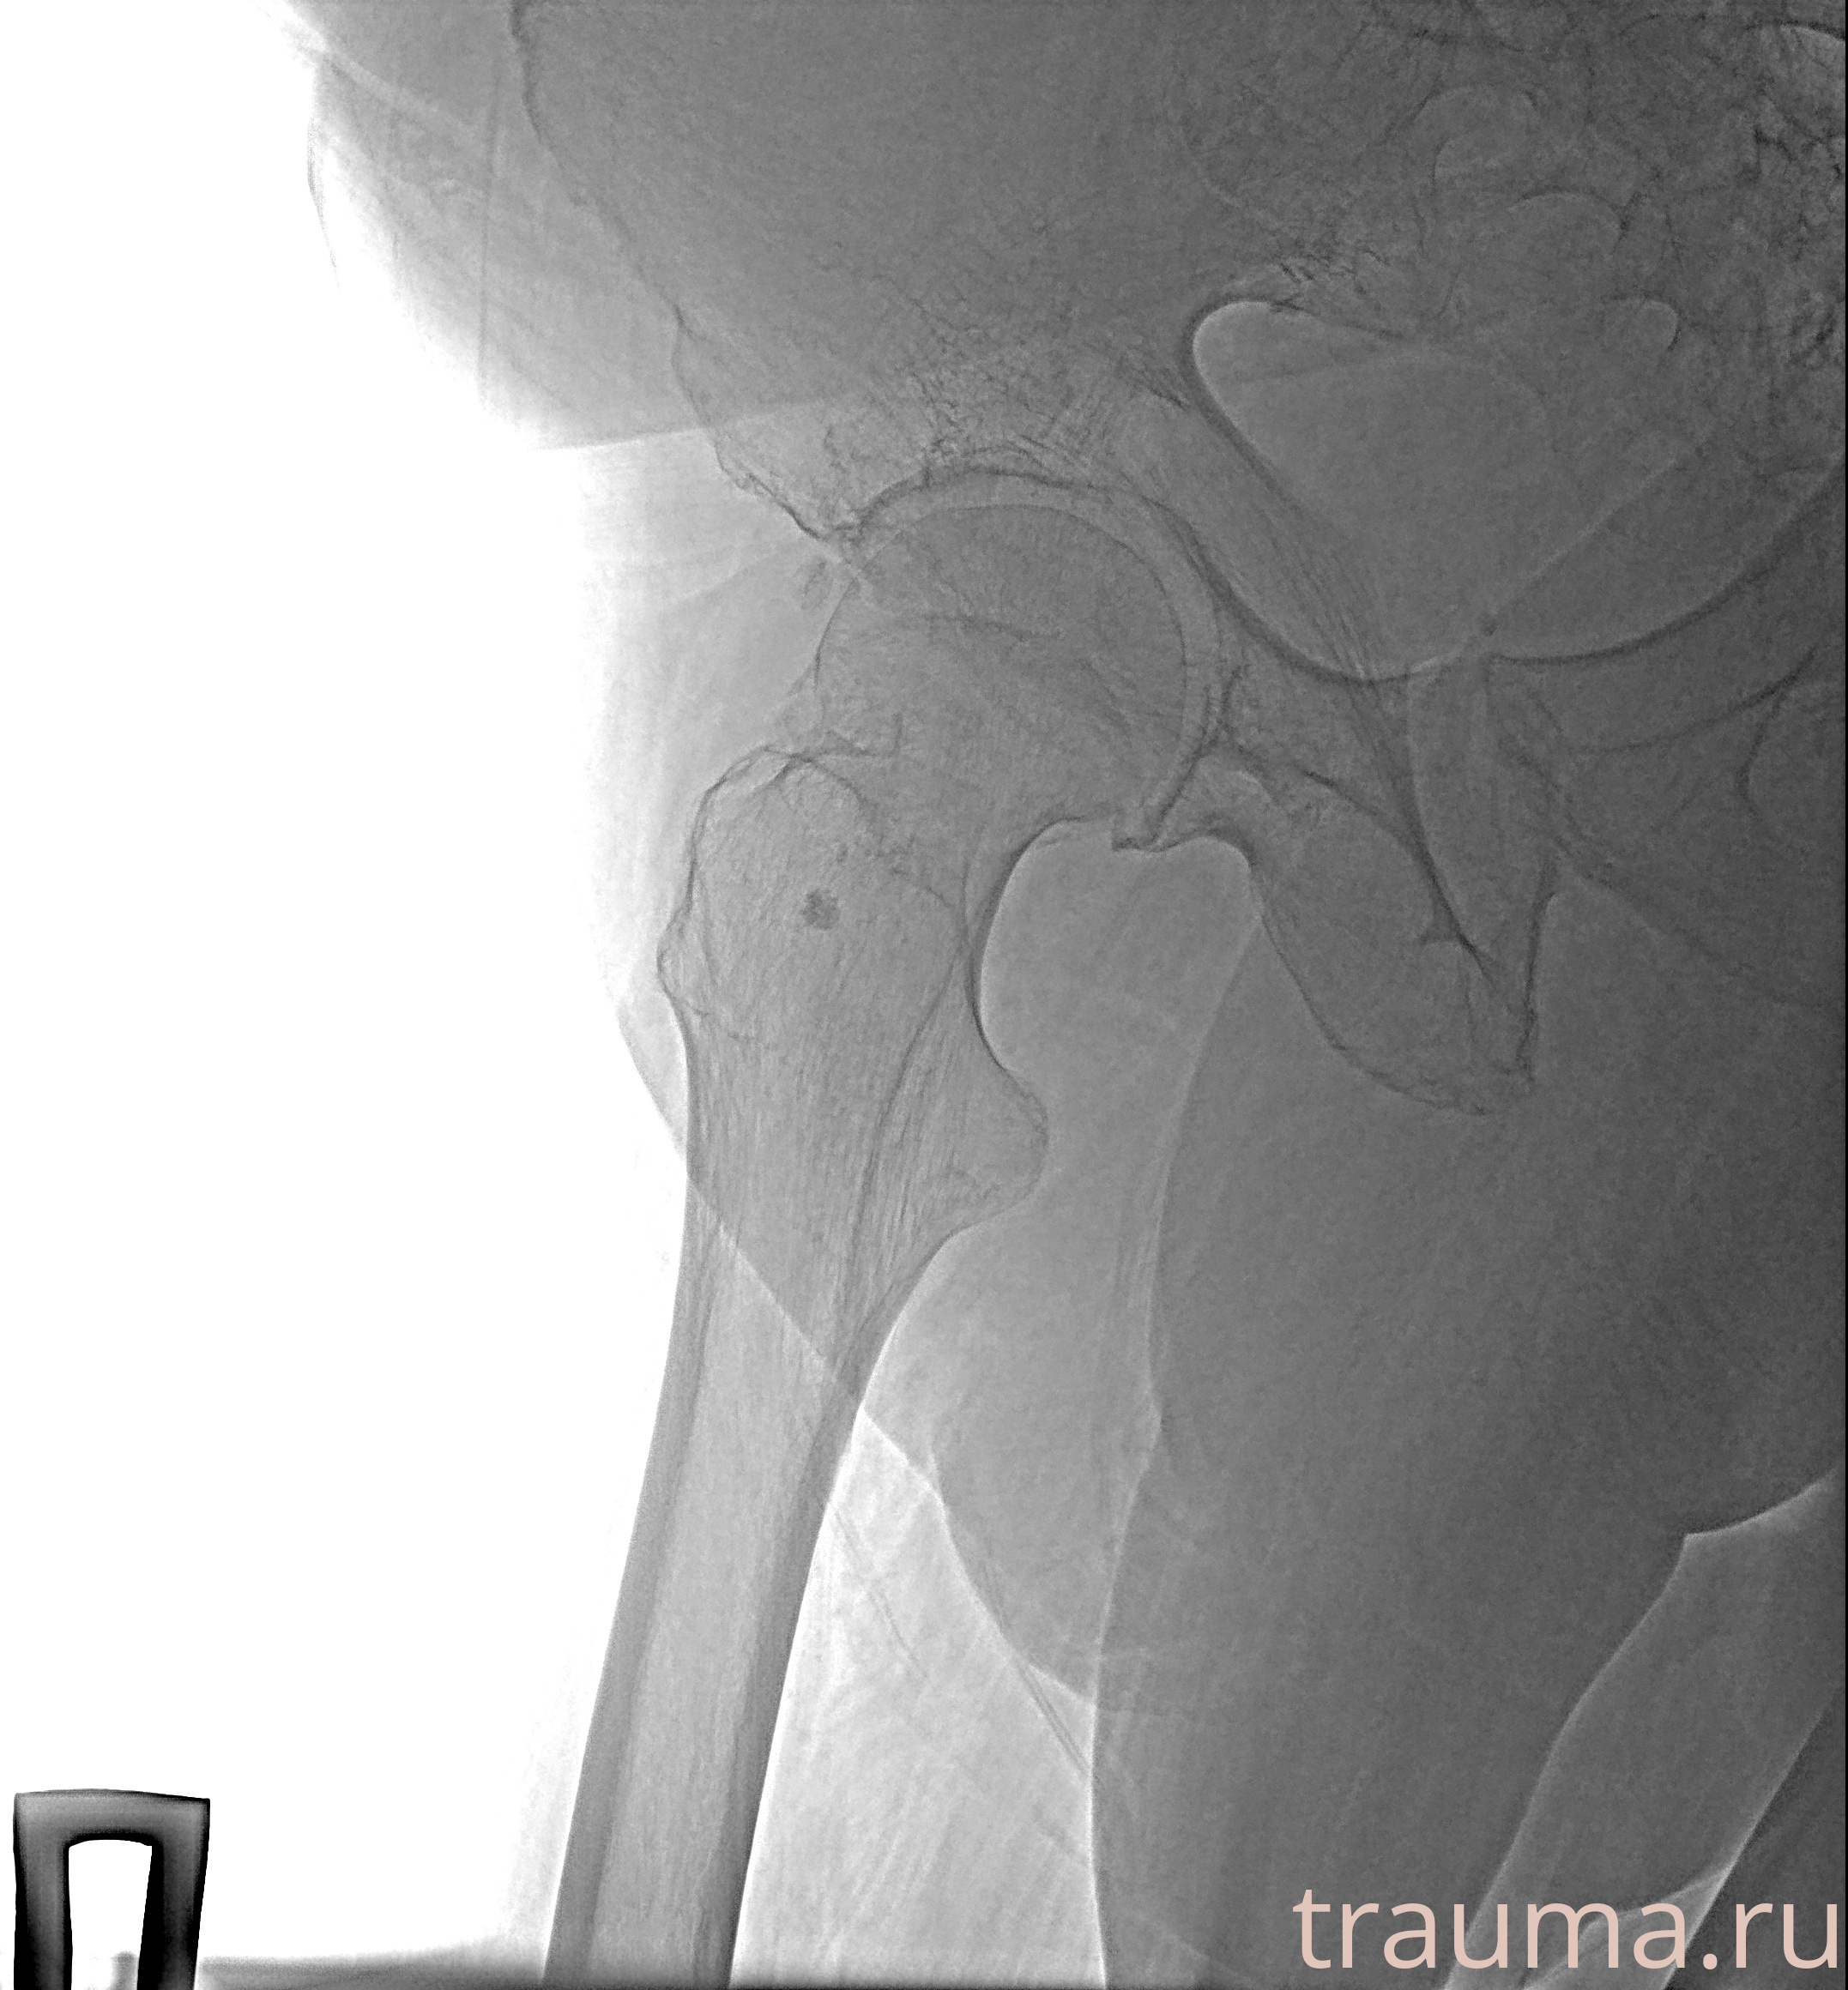

Рентгенограммы

Рентген на дому: по вашему адресу приезжает врач-рентгенолог, травматолог-ортопед с мобильным рентгеновским аппаратом, проводит диагностику травмы или заболевания, делает необходимые рентгенограммы, дает рекомендации по дальнейшему лечению. Получить качественные снимки в домашних условиях возможно благодаря уникальной методике, разработанной МосРентген Центром для института  Склифосовского